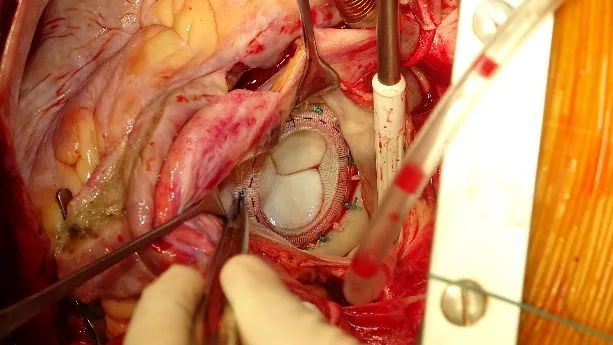

术中采取仰卧位,正中开胸,建立体外循环,处理冠脉问题后,经房间沟进入左心房,探查二尖瓣情况,保留部分二尖瓣瓣叶后,行二尖瓣置换手术。经测瓣器精准测量瓣环大小后,选择植入一枚29mm金仕信力®X-LINK®生物瓣膜。随后,陶院长将缝合线穿过信力瓣膜柔软的缝合环,生物瓣膜推入二尖瓣位后,取下持瓣手柄,打结、缝合,并行房颤MAZE手术,关闭切口、排气,停体外循环,关胸一气呵成。超声显示瓣膜开合良好,生物瓣机能正常。术后顺利脱机拔管,患者神志清晰,呼吸循环稳定。